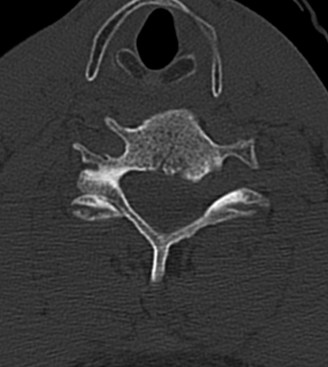

The diagnostic imaging workup for this patient spanned his initial presentation at age 15 and his subsequent return at age 20, providing a textbook illustration of the natural history of untreated isthmic spondylolysis. During his initial visit, standard weight-bearing anteroposterior (AP), lateral, and bilateral oblique radiographs of the lumbar spine were obtained. The lateral radiograph demonstrated a normal lumbar lordosis and preserved L5-S1 disc space height, with no evidence of anterior translation (spondylolisthesis). However, the oblique radiographs revealed the pathognomonic "collar on the Scotty dog" sign. The "Scotty dog" represents the posterior elements of the vertebra, where the nose is the transverse process, the eye is the pedicle, the front leg is the inferior articular process, and the neck is the pars interarticularis. A radiolucent line across the neck confirmed the presence of bilateral L5 pars defects.

Clinical & Radiographic Imaging Archive